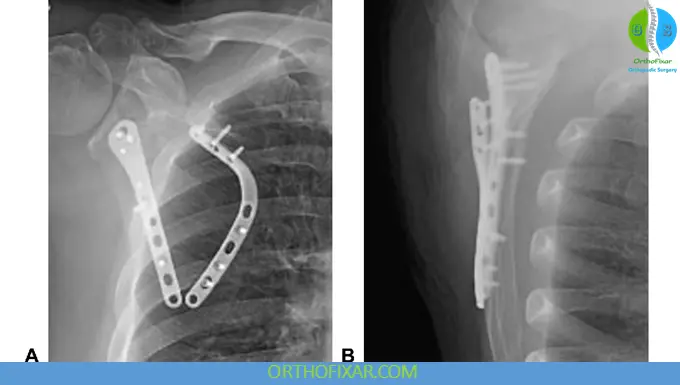

Operative Management

Indications include:

- Intra-articular glenoid fractures (>25% involvement)

- Articular step-off >5 mm

- Scapular neck:

- 40° angulation

- 1 cm medial displacement

Surgical Considerations

Positioning:

- Lateral (common for body/neck fractures)

- Supine or beach chair (depending on approach)

Surgical approaches:

- Anterior (deltopectoral): glenoid/coracoid

- Posterior (Judet approach): body/neck

- Superior: acromion